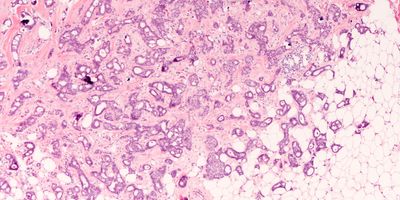

A framework for designing digital pathology systems that balance throughput, budgets, and turnaround times